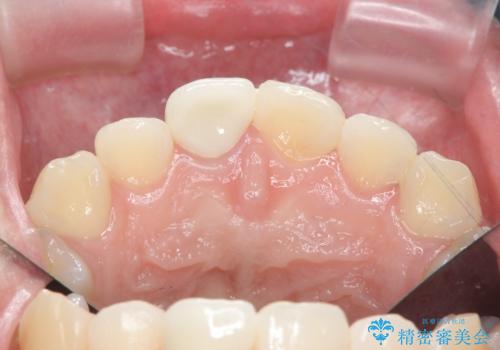

歯ぐきにできものができた 前歯の色調改善

- 歯ぐきに、にきびのようなものができ治らない、と治療を希望され来院されました。

歯髄の検査、X線検査より神経の失活が確認されたので、根管治療・ファイバーコア築盛 ・ジルコニアクラウンの製作、と治療を進めます。

根管治療を行ったことで、歯ぐきのできものは治癒し再発をしなくなりました。